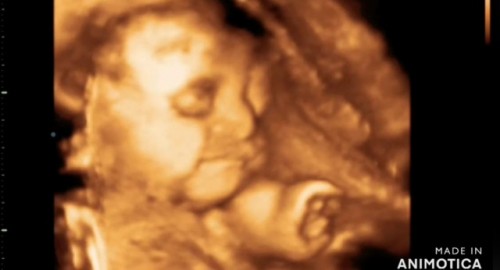

ลูกสาวค่ะซาวด์4มิติ